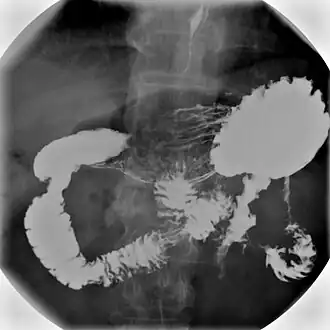

Plaats van de maag in het lichaam

1. slokdarm, 2. , 3. dunne darm, 4. appendix, 5. blindedarm, 6. karteldarm, 7. endeldarm, 8. anus